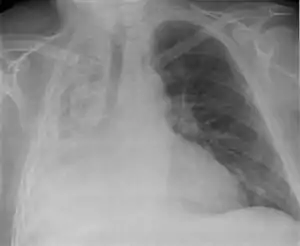

Clinically significant atelectasis is generally visible on chest X-ray; findings can include lung opacification and/or loss of lung volume. Post-surgical atelectasis will be bibasal in pattern. Chest CT or bronchoscopy may be necessary if the cause of atelectasis is not clinically apparent. Direct signs of atelectasis include displacement of interlobar fissures and mobile structures within the thorax, overinflation of the unaffected ipsilateral lobe or contralateral lung, and opacification of the collapsed lobe.In addition to clinically significant findings on chest X-rays, patients may present with indirect signs and symptoms such as elevation of the diaphragm, shifting of the trachea, heart and mediastinum; displacement of the hilus and shifting granulomas.[10]

It is usually associated with accumulation of blood, fluid, or air within the pleural cavity, which mechanically collapses the lung. This is a frequent occurrence with pleural effusion, caused by congestive heart failure (CHF). Leakage of air into the pleural cavity (pneumothorax) also leads to compression atelectasis.[12]